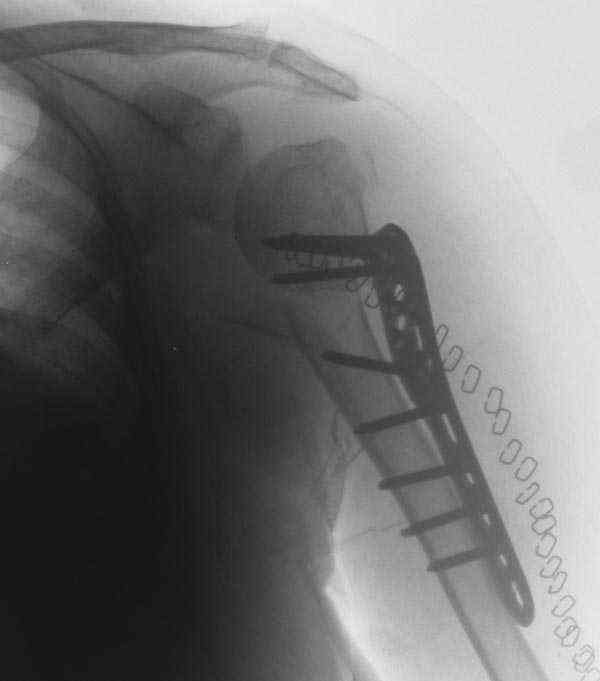

The fracture is completely displaced in the axial view. It is probably possible to align it with the patient in the vertical position, i.e. sitting or standing. However, I would use a locking plate for the tremendous pain relief it offers.

I am attaching the radiographs of the mother of a doctor. She has chronic renal failure for >10 years, diabetes mellitus and coronary artery disease. Age 62. She was offered the options of non-surgical management in a sling and surgery with a locking plate. She was given Tramadol for pain relief. Five days after injury, patient requested surgery, because of pain, inability to move without pain.

The reduction is not perfect. The patient is very small made, and it was difficult to bring the plate proximally without impingement in abduction.

Pain relief after surgery was early and sustained.